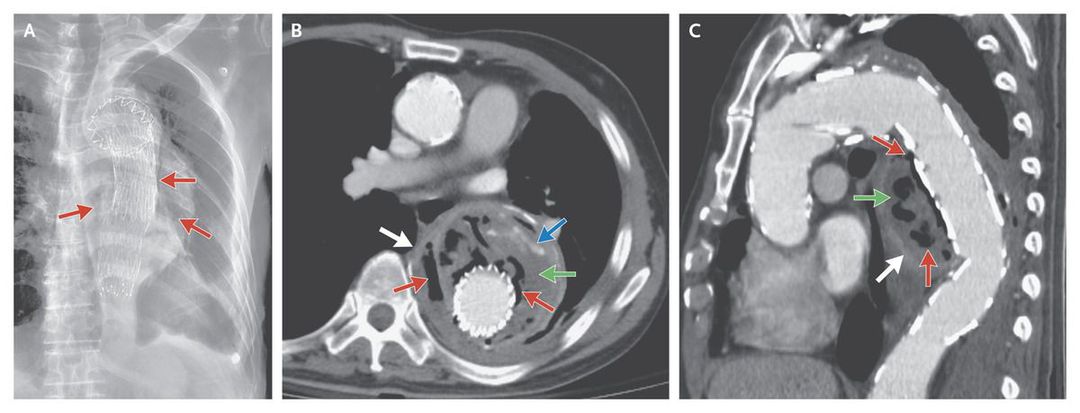

A 75-year-old man presented to the emergency department with a 5-day history of back pain and intermittent fever. He had undergone endovascular aortic repair of a thoracic aortic aneurysm 7 years previously. He had poor oral hygiene and dental caries. Physical examination revealed diminished breath sounds on the left side. Blood tests revealed leukocytosis. A radiograph of the chest showed changes consistent with stent-graft repair of the thoracic aortic aneurysm, gas around the stent graft (Panel A, arrows), and pleural effusion on the left side. Computed tomography revealed multiple findings involving the aneurysmal sac, including gas bubbles, fluid collection, endoleak (leakage of blood into the aneurysm), and enhancement of the aneurysmal wall (Panel B, axial view, and Panel C, oblique sagittal view; red, green, blue, and white arrows, respectively). Blood culture yielded Streptococcus oralis. The fever and leukocytosis subsided gradually after the administration of intravenous penicillin G. Surgical excision of the infected segment of aorta was planned, but on the 20th hospital day, the patient had a sudden episode of massive bloody vomiting and died. Emphysematous aortitis is a life-threatening complication after endovascular aortic repair. In our patient, septicemia from poor oral hygiene was the presumed cause of this late complication.